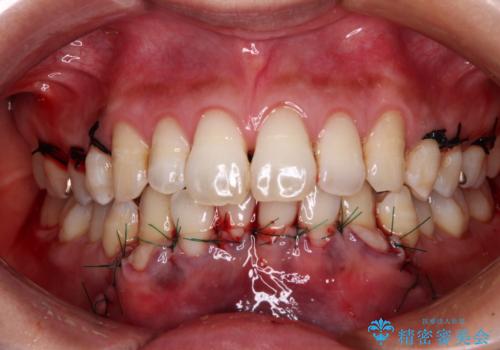

- 年々歯肉退縮が進行することを気にして来院された患者様です。

歯肉が菲薄であることが経年的な進行の原因であることが推察されたため、上顎からの結合組織移植術(CTG)により、歯根の被覆を行うとともに、歯肉の厚みを増すことで将来の退縮リスクを抑制することとしました。

被覆量が不十分の場合には、追加で手術を行うことで患者様の了解を得ました。

上顎両側から歯肉を採取したたため、術後は痛みや出血で辛い思いをされましたが、1回の処置で満足のいく結果となりました。

根面被覆量も改善できましたが、歯肉の厚みが十分なものとなったことで、今後の歯肉退縮に歯止めをかけることができました。